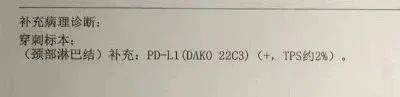

经淋巴转移灶穿刺活检,符合转移性非小细胞肺癌,大细胞肺癌不能排除,后经省医院病理会诊,会诊意见:倾向腺癌,且不支持鳞癌及神经内分泌癌,免疫组化结果 tps 约2%。

图片来源:患者提供